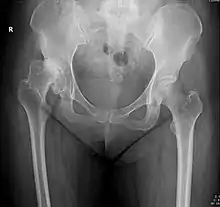

X-ray of the hips of a 40-year-old female, with dysplasia of her right hip.